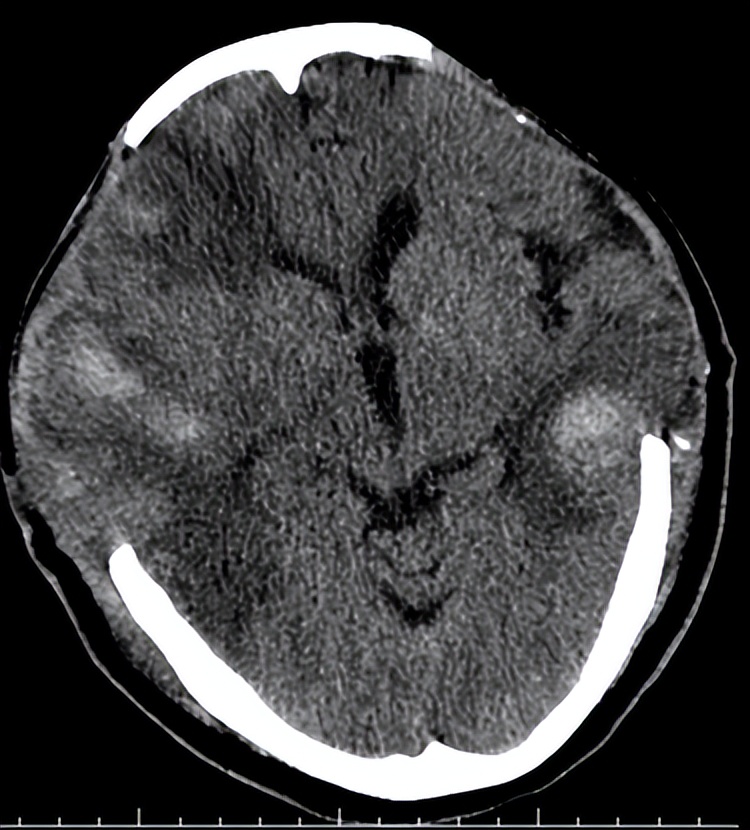

06-08术后第一天复查头CT示:

术后第一天第二天,患者呈昏迷状,反应较前变差,但生命体征平稳。